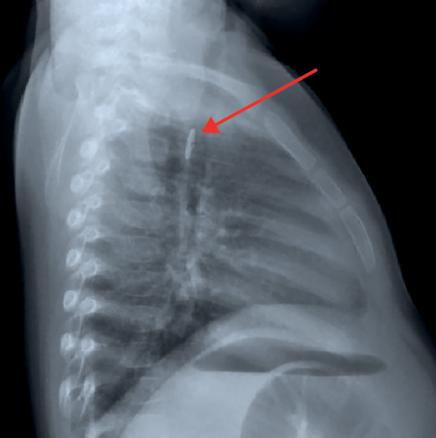

La radio standard, prescrite en urgence, met en évidence un corps étranger (CE) situé au niveau du carrefour aéro-digestif (fig. 1). Une ablation par laryngoscopie est préconisée.

Le bilan radiologique comporte des clichés cervicaux, thoraciques et éventuellement un abdomen sans préparation. En cas de CE radio-opaque (objet métallique, pièce de monnaie...), il permet de déterminer sa taille, sa nature et sa localisation, de dépister d’éventuelles complications et de surveiller sa progression dans le tube digestif. Il n’est pas systématique en cas d’incarcérations d’aliments dans la muqueuse digestive.